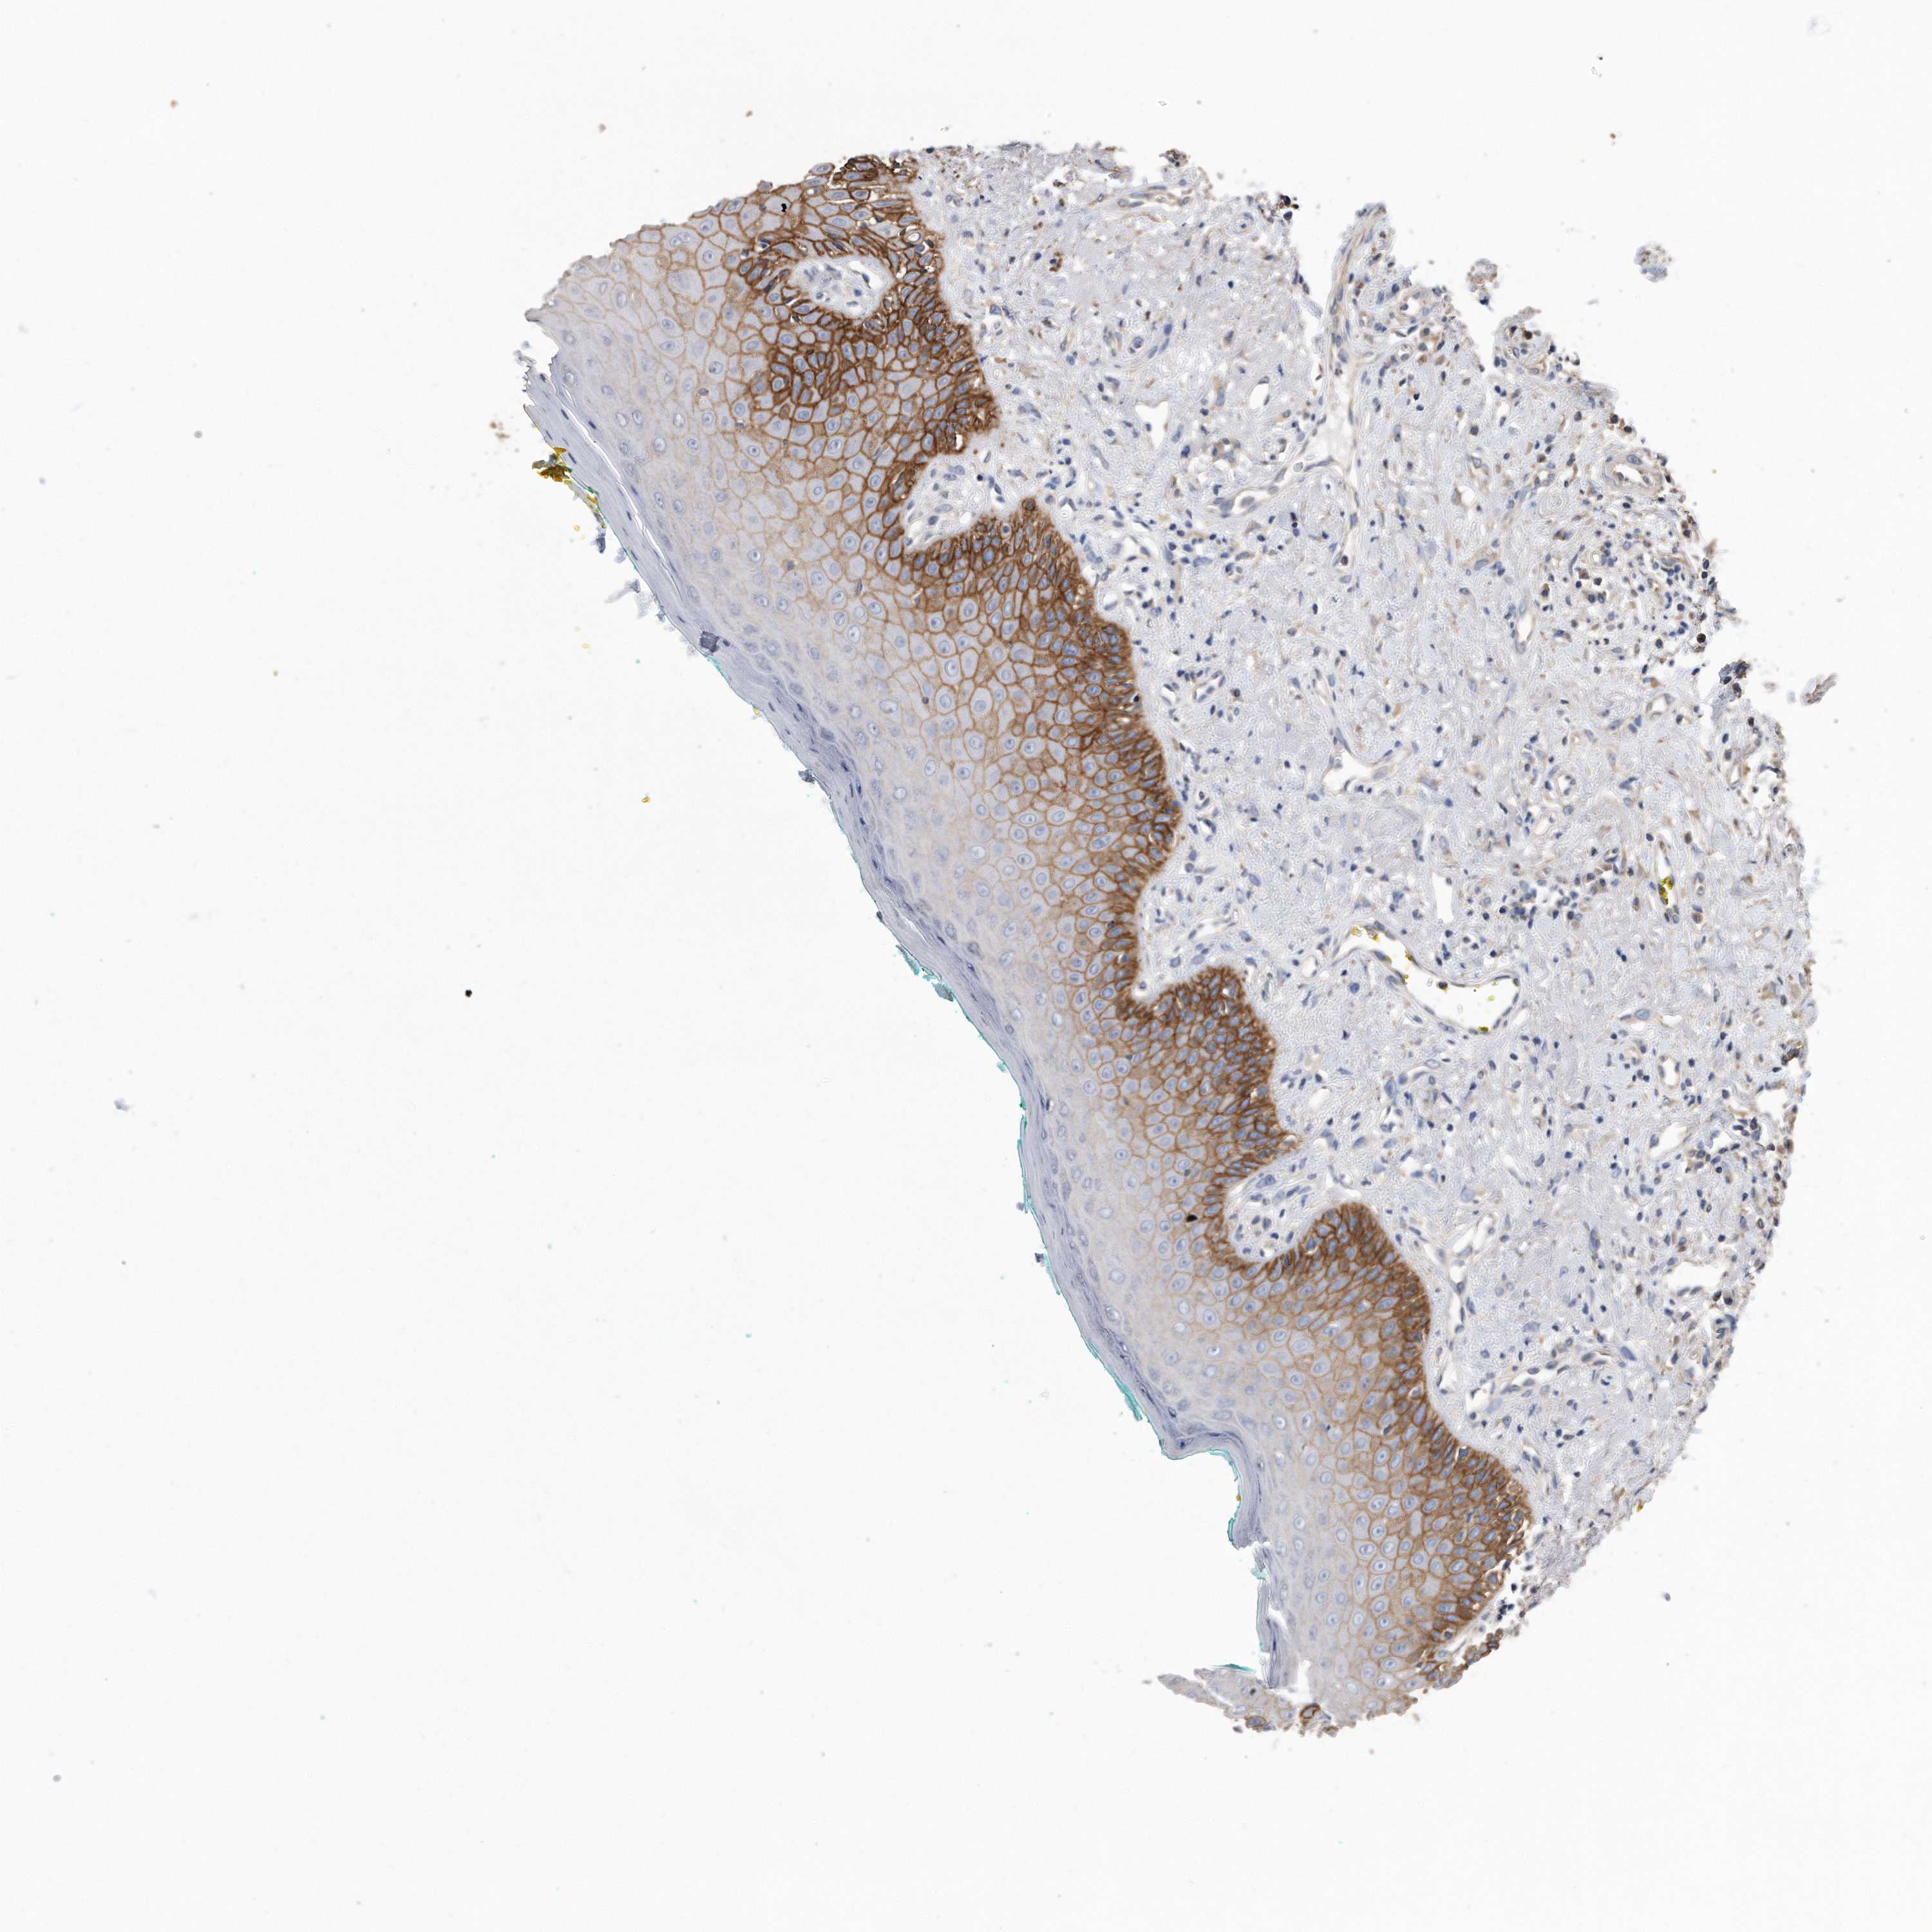

CDCP1